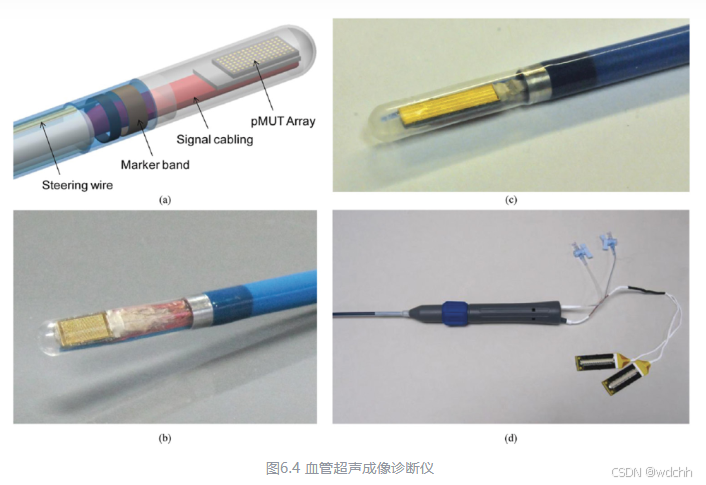

该团队在2014年发表了一篇环形PMUT阵列的研究,发表在JMEMS上。该环形PMUT阵列由1261个振元构成,用于血管内超声成像。

振膜直径25 μm,振元圆心间距30 μm,圆形阵列由1261个振元组成,整个阵列直径1.2 mm。液体中谐振频率18.6 MHz。压电材料为750 nm的AlN。带宽4.9 MHz,空气中振幅2.5 nm/V。

这篇文章写的很深入,对填充系数、灵敏度、FOM有关的的重要公式都进行了介绍,对器件的振动模型、等效电路模型都有分析。结构上,利用多晶硅作为牺牲层,释放内部腔体。2 μm ×4 μm 在边上的方形通孔,或2 μm直径在PMUT中心的圆心通孔,3 μm的parylene密封,整个工艺过程也是相当复杂的。血管内超声成像效果十分好。

6.3血管内超声成像

血管内超声成像(IVUS)为心血管疾病的诊断搭了一条新路,该技术搭载超声探头和微电机,钻进血管内部,成像出血管侧壁的图像,对于因钙化、纤维化等造成的血栓等病变进行诊断。

由于是血管内成像,体积是IVUS的最大限制,因此微机械超声换能器是当前唯一的选择。IVUS有机械旋转成像和相控阵成像,其原理和区别也和类似于扫描式和静态式成像。它们的核心都在于体积小,振元密度大,这是只有PMUT才能完成的任务。